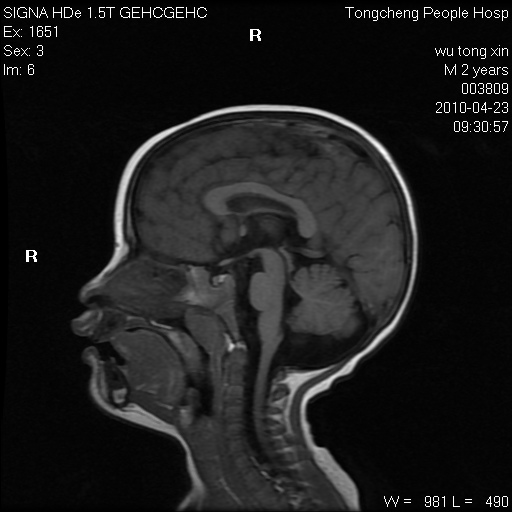

以下是引用赵物学在2010-4-25 12:43:00的发言:[br]巨脑回[br]侧脑室后角低密度影考虑hie或肾上腺脑白质营养不良?[br][br][本贴已被 赵物学 于 2010-4-25 12:51:28 修改过]

以下是引用gaoxiao在2010-4-25 16:54:00的发言:[br]巨脑回畸形。脑白质髓鞘化不良

以下是引用pujunzhi在2010-4-25 21:35:00的发言:[br]考虑 1双侧大脑皮质发育不良 2轻度脑积水 3双侧脑室后角旁片状长t1长t2信号,需继续观察,因为正常小儿此处脑白质的髓鞘化时间可以延迟到4-6岁,才显示正常。